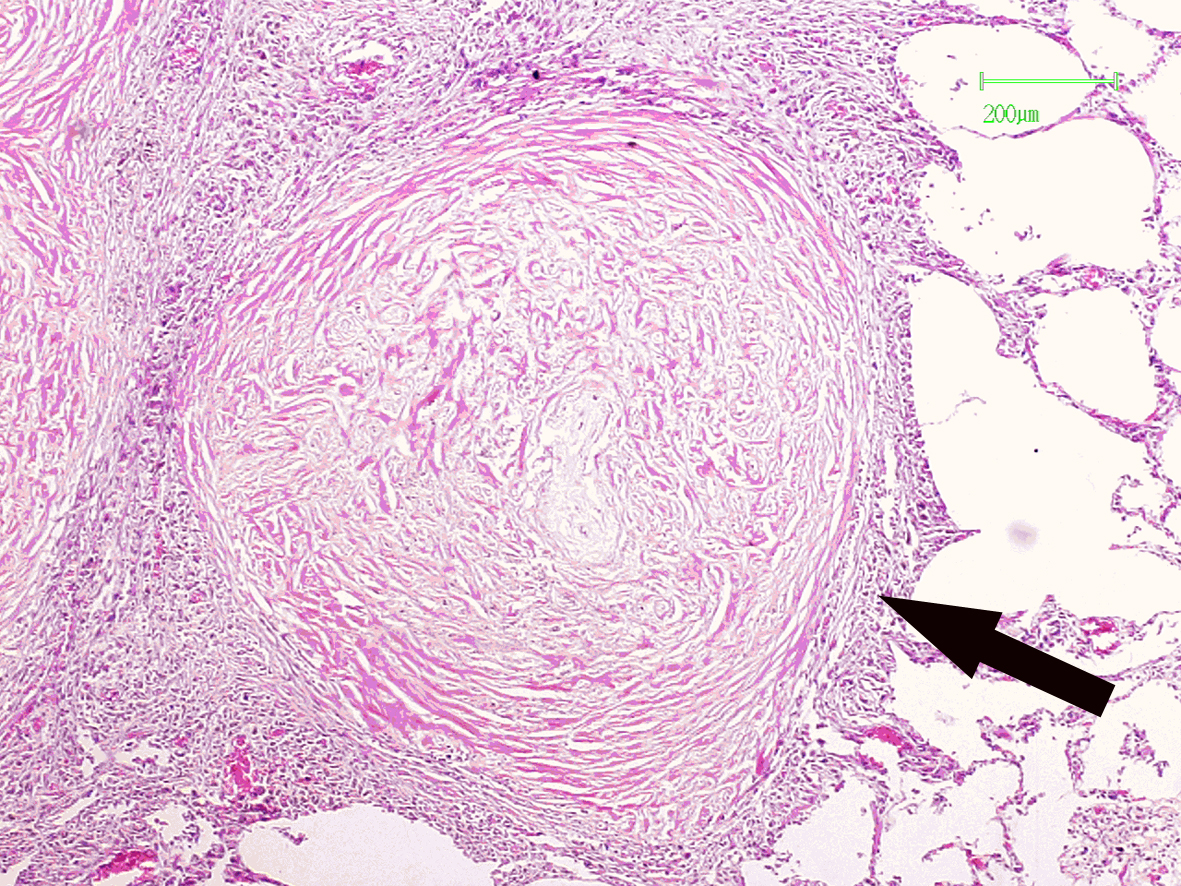

5.矽肺节